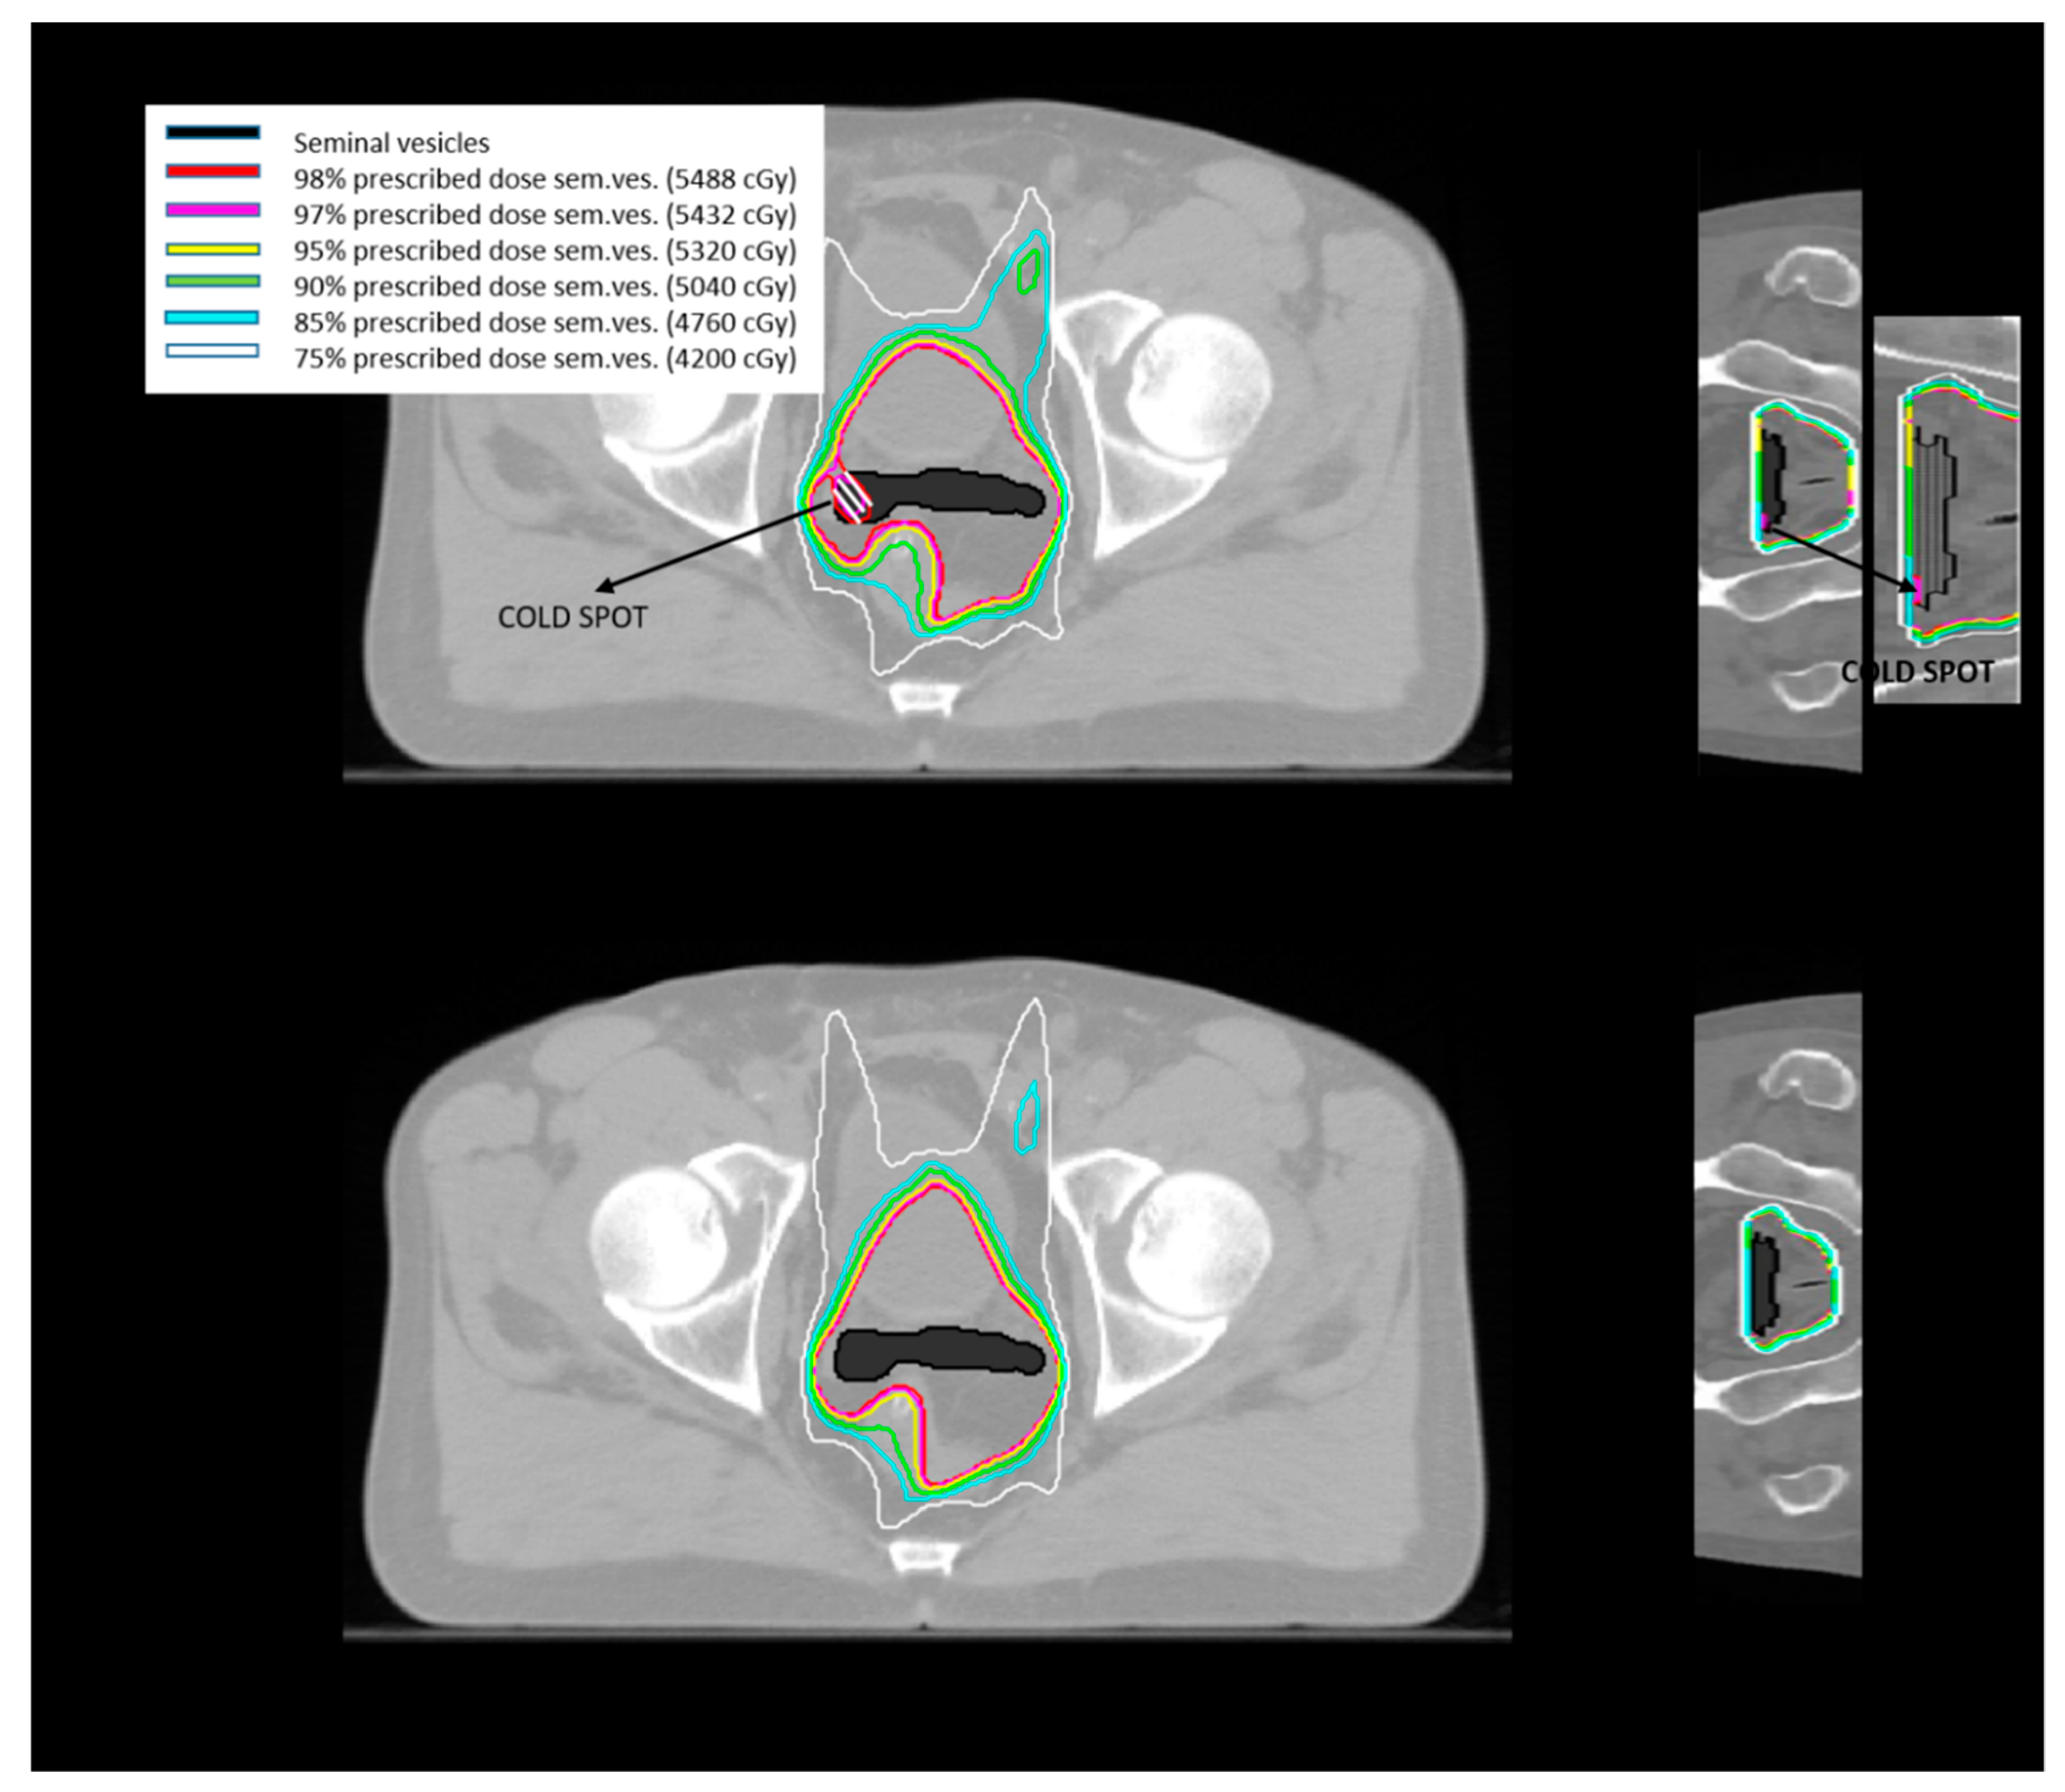

- Tomé, W.A.; Fowler, J.F. On cold spots in tumor subvolumes. Med. Phys. 2002, 29, 1590–1598. [Google Scholar] [CrossRef]